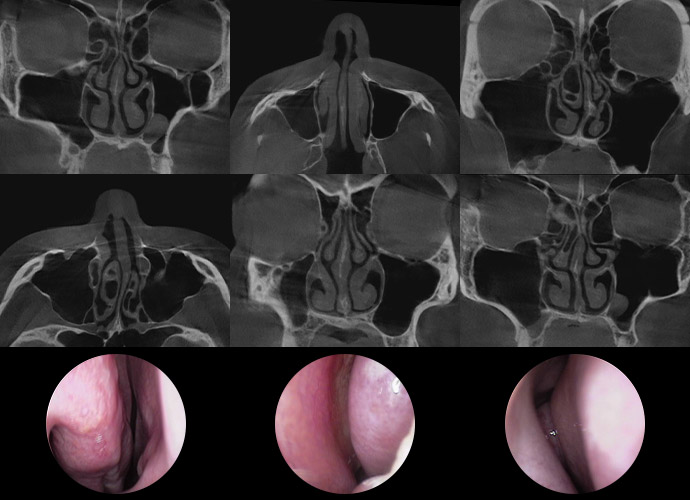

3D-CT and Precision

Nasal Endoscopy

Detailed Diagnosis to

Examine

Nasal Interior in Depth!

3D-CT Examination

Before surgery, a 3D-CT scan is conducted to accurately capture internal

nasal structures, including the skeletal structure, nasal bone width, septal

condition, asymmetry, and inferior turbinate size, which are difficult to

observe with the naked eye

A 3D-CT scan is conducted before surgery to

precisely capture internal nasal structures that are

difficult to observe with the naked eye, and an

ENT specialist reviews the results to assess the

condition and determine the need for functional

improvements.

Precision Nasal Endoscopy

Precision nasal endoscopy is performed before surgery to directly

observe internal nasal structures, as 3D-CT provides an overview

for functional nasal surgery.

It is an examination performed before surgery to

directly observe the internal nasal structures and

accurately assess conditions that are difficult to

identify with 3D-CT, such as the state of the nasal

mucosa, polyps, nasal polyposis, and postnasal

drip inflammation.